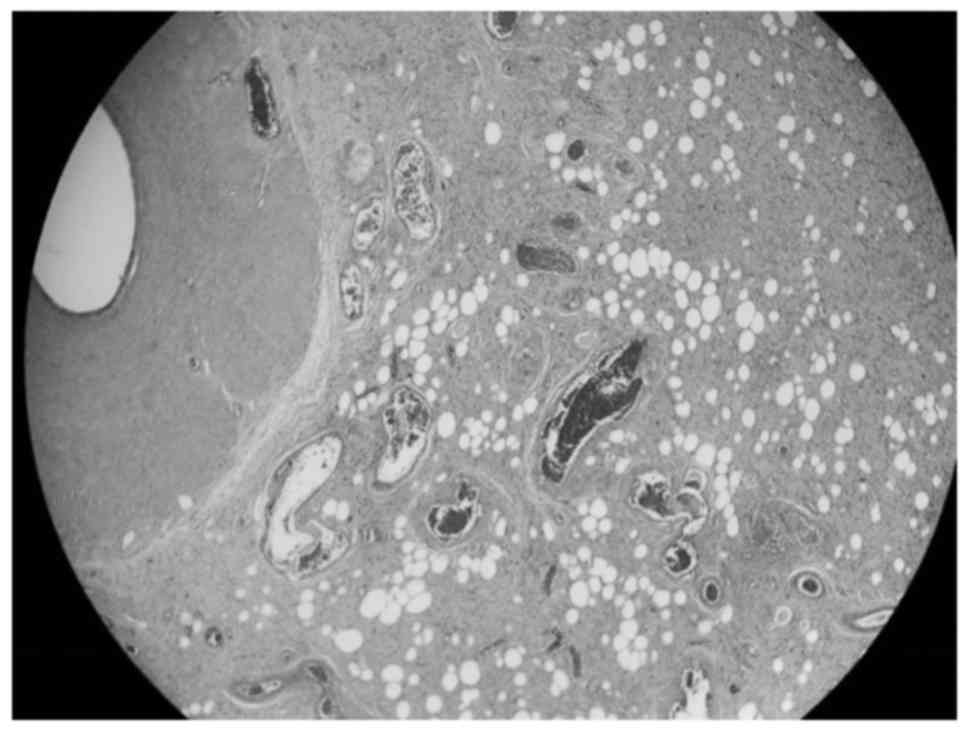

Intraoperatively, following dissection of the spermatic cord, a multi-lobulated, encapsulated, yellow mass was identified within the cord. The mass appeared to infiltrate surrounding soft tissue structures, such as muscle and the external tunica vaginalis. Further dissection and delivery of the right testis demonstrated an atrophic testis with no evidence of local invasion. After a thorough on-site evaluation, surgical resection was delayed to permit better assessment of the disease and to obtain patient consent for possible orchiectomy. An incisional biopsy of the mass was performed, and pathological analysis revealed a well-differentiated liposarcoma of the sclerosing type (Fig. 1).

Figure 1.

Histological examination of the spermatic cord tumor revealed mature vacuolated adipocytes with variation in cell size and fibrous septa containing atypical stromal cells, consistent with a well-differentiated liposarcoma of the sclerosing type (hematoxylin and eosin staining; magnification, ×4).